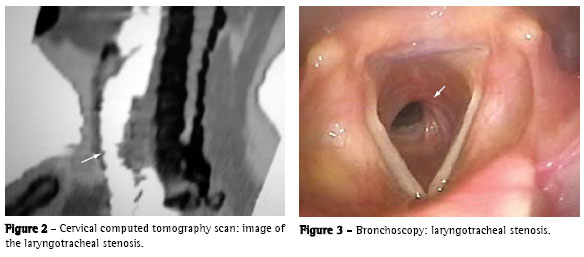

A 56-year-old, white female patient, who was a nonsmoker, was referred to the Londrina University Hospital after having been bronchoscopically diagnosed with tracheal stenosis and severe obstructive respiratory disorder. The patient had been presenting progressive dyspnea for six years and had been treated unsuccessfully for 'bronchitis'. A cervical tomography scan with reconstruction revealed a 2-cm stenosis at the end of the larynx and trachea as well as partial (60%) obstruction of the tracheal lumen (Figure 2). Dilatation was unsuccessful due to the severe fibrosis. The patient then underwent surgical resection and tracheoplasty with end-to-end anastomosis. The anatomopathological examination revealed a chronic inflammatory abnormalities. The postoperative evolution was favorable, and the patient remained asymptomatic during an outpatient follow-up period of one year and three months.

A 56-year-old, white female patient, who was a nonsmoker, sought treatment after experiencing progressive dyspnea and cough for six years. Her condition had deteriorated in the last six months. The patient had been treated unsuccessfully for 'bronchitis'. Bronchoscopy revealed laryngotracheal stenosis (3-4 mm thick) with partial (50%) obstruction of the tracheal lumen (Figure 3). Dilatation was performed using a rigid bronchoscope, and the biopsy revealed a nonspecific chronic inflammatory process. A three-week course of corticosteroid therapy was prescribed, and the patient remained asymptomatic during an eight-month outpatient follow-up period.